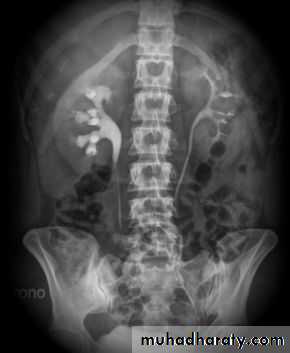

Normal IVU series

Failure of contrast to pass to ureters due to both sided mid ureteric stones

LT sided upper Ureteric stones

Bilateral HU + HN